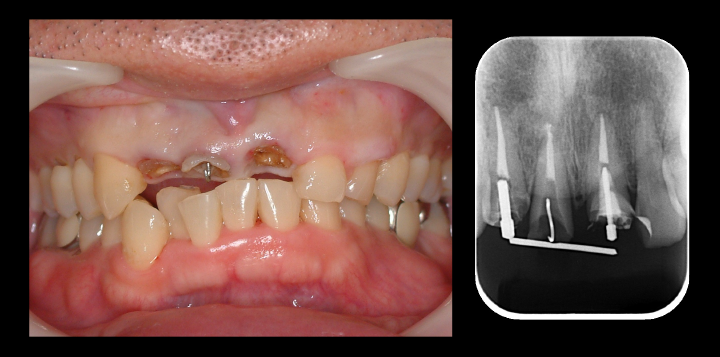

術前および術後の比較

before before |

after after |

before before |

after after |

術前と術後の比較写真です。

歯茎の下の方まで虫歯でしたが歯茎の上までしっかりと健康な歯の部分を出すことができました。

歯の形を整え最終的な被せもの被せた時の口腔内写真です。

before before |

after after |

術前、術後の比較写真です。

歯の保存と見た目の改善もでき、患者さんも満足してくださいました。